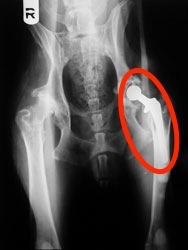

- Due to expense and invasiveness, this is the “last resort” for dysplastic dogs, but has the best results, completely restoring hip joint function and eliminating pain.

- The diseased hip joint is removed and replaced with an artificial joint that lasts for the lifetime of the dog.

3 Photo Credit: Veterinary Practice News